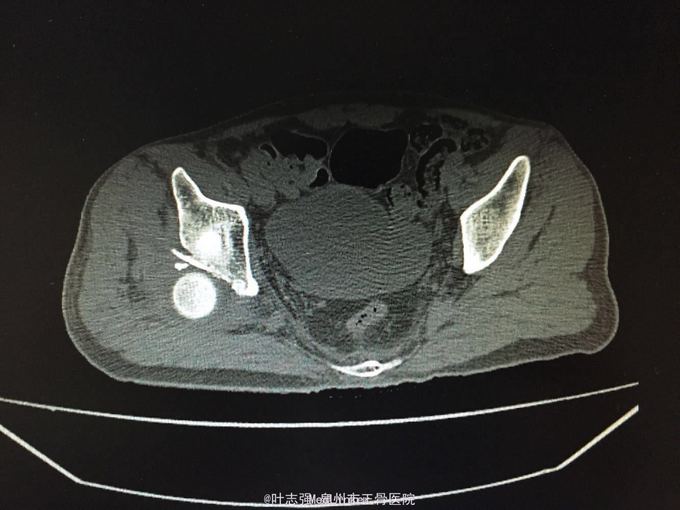

髋臼骨折伴髋关节后脱位ORIF

车祸致左髋部疼痛、活动受限1天。 53岁男性

左髋臼骨折伴髋关节后脱位 行生命支持,股骨髁上骨牵引,

股骨头坏死概率?